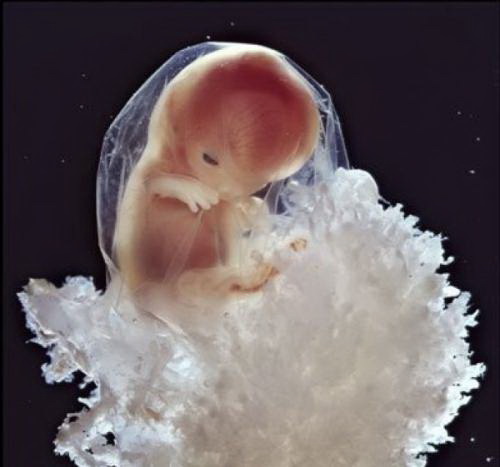

Предлагаю Вашему вниманию уникальный репортаж из женского тела.

Эти уникальные фотографии сделаны шведским фотографом Леннартом Нильсоном ещё в 1965 году. Сам фотограф родился в 1922 году и стал первым, кто при помощи специального оборудования и фотокамер, смог проникнуть внутрь женского тела и снять весь процесс зарождения новой жизни.

Первые фотографии эмбриона появились в печати ещё в 1953 году, и это событие вдохновило фотохудожника на создание новых работ.

Для того, чтобы показать развитие человека с самого начала, он поместил микрокамеру и микроосветитель на конец трубки цистоскопа, которым осматривают мочевой пузырь, и снял свои уникальные фотографии прямо оттуда, откуда люди делают первый шаг в мир...

Вот она - наша история зарождения жизни!